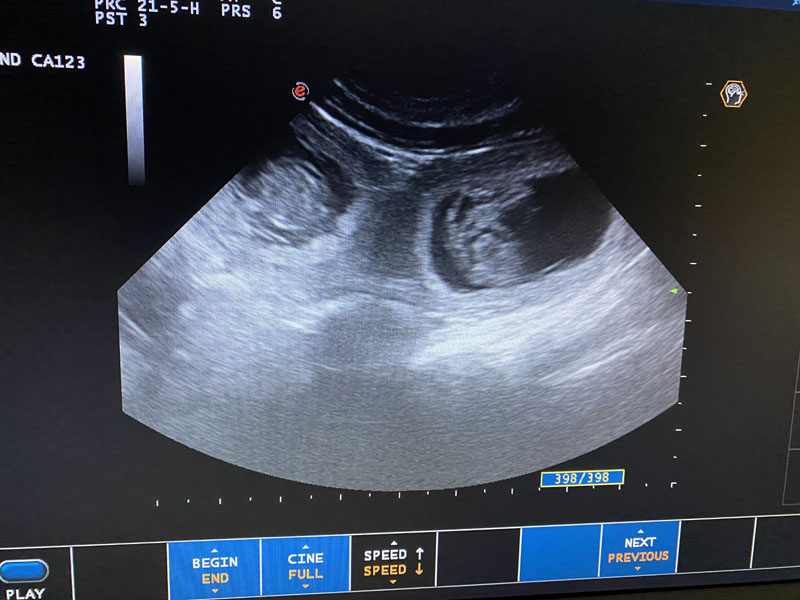

Det finns många valpar i magen enligt ultraljudet!